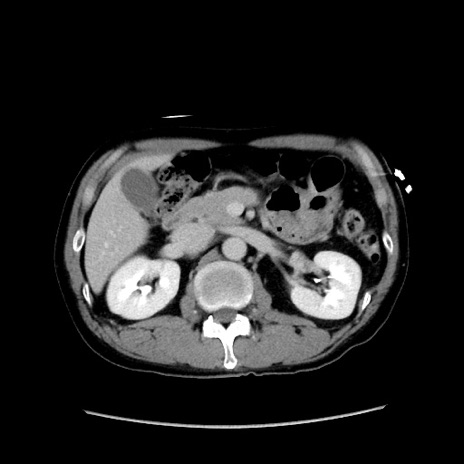

症例37(横断像)

冠状断像

【症例】40歳代 男性

【主訴】腹痛

【現病歴】4時間ほど前に電車に乗車中に臍部上より腹痛出現。徐々に増悪し起立困難となり、救急外来受診。生ものは数日食べていない。今朝お雑煮を食べた。

【身体所見】BT 36.8℃、BP 117/84mmHg、HR 91/min、SpO2 97%、苦悶様、腹部:臍上部広範囲圧痛あり、反跳痛±

【データ】WBC 8100、CRP 0.03